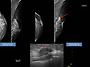

| 유방, 갑상선 초음파 스캔 및 병리과정.. | sonoedu | 280 | 26.02.07 |